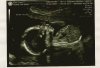

I can't wait to see everyone's u/s pics! I love looking at them!